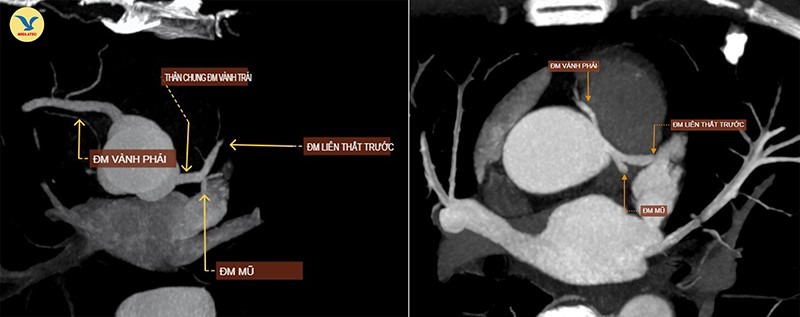

Hình ảnh chụp CTA. Ảnh trái: Một người bình thường, hai nhánh động mạch vành xuất phát từ hai gốc riêng biệt. Ảnh phải: Hai nhánh động mạch vành của bệnh nhân xuất phát chung một gốc

Kết quả chụp CTA cho thấy, bệnh nhân mắc một bất thường bẩm sinh hiếm gặp là động mạch vành đơn (Single Coronary Artery), type LII-B. Dị tật này khiến cả hai nhánh động mạch vành trái và phải xuất phát chung từ một gốc duy nhất thay vì hai gốc riêng biệt.

Đáng chú ý, nhánh động mạch vành phải của ông T. đi theo hướng bất thường, bị kẹp giữa thân động mạch phổi và động mạch chủ, gây hẹp bẩm sinh khoảng 45% đường kính. Đây chính là nguyên nhân khiến ông bị đau ngực khi gắng sức, dấu hiệu cảnh báo thiếu máu cơ tim.

Bình thường, tim có hai động mạch vành trái và phải xuất phát từ hai vị trí riêng biệt trên xoang vành của động mạch chủ, dẫn máu nuôi cơ tim. Nhưng ở người mắc dị tật này, chỉ có một gốc động mạch vành xuất phát từ một vị trí duy nhất rồi tỏa nhánh đi nuôi toàn bộ tim.

Type LII-B, phân loại theo hệ thống Lipton, được xếp vào nhóm có đường đi nguy cơ cao. Trong biến thể này, nhánh động mạch vành phải xuất phát từ xoang Valsalva bên trái, sau đó đi qua giữa động mạch chủ và thân động mạch phổi, một vị trí dễ bị chèn ép, đặc biệt khi gắng sức, làm giảm lượng máu nuôi tim và có thể dẫn tới đột tử.